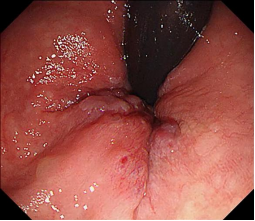

消化道早癌的病例展示(经内镜手术或活检证实):

胃窦的腺癌 行ESD治疗

术中见较粗穿支血管,裸化后凝除,最终高效、安全的切除病灶。